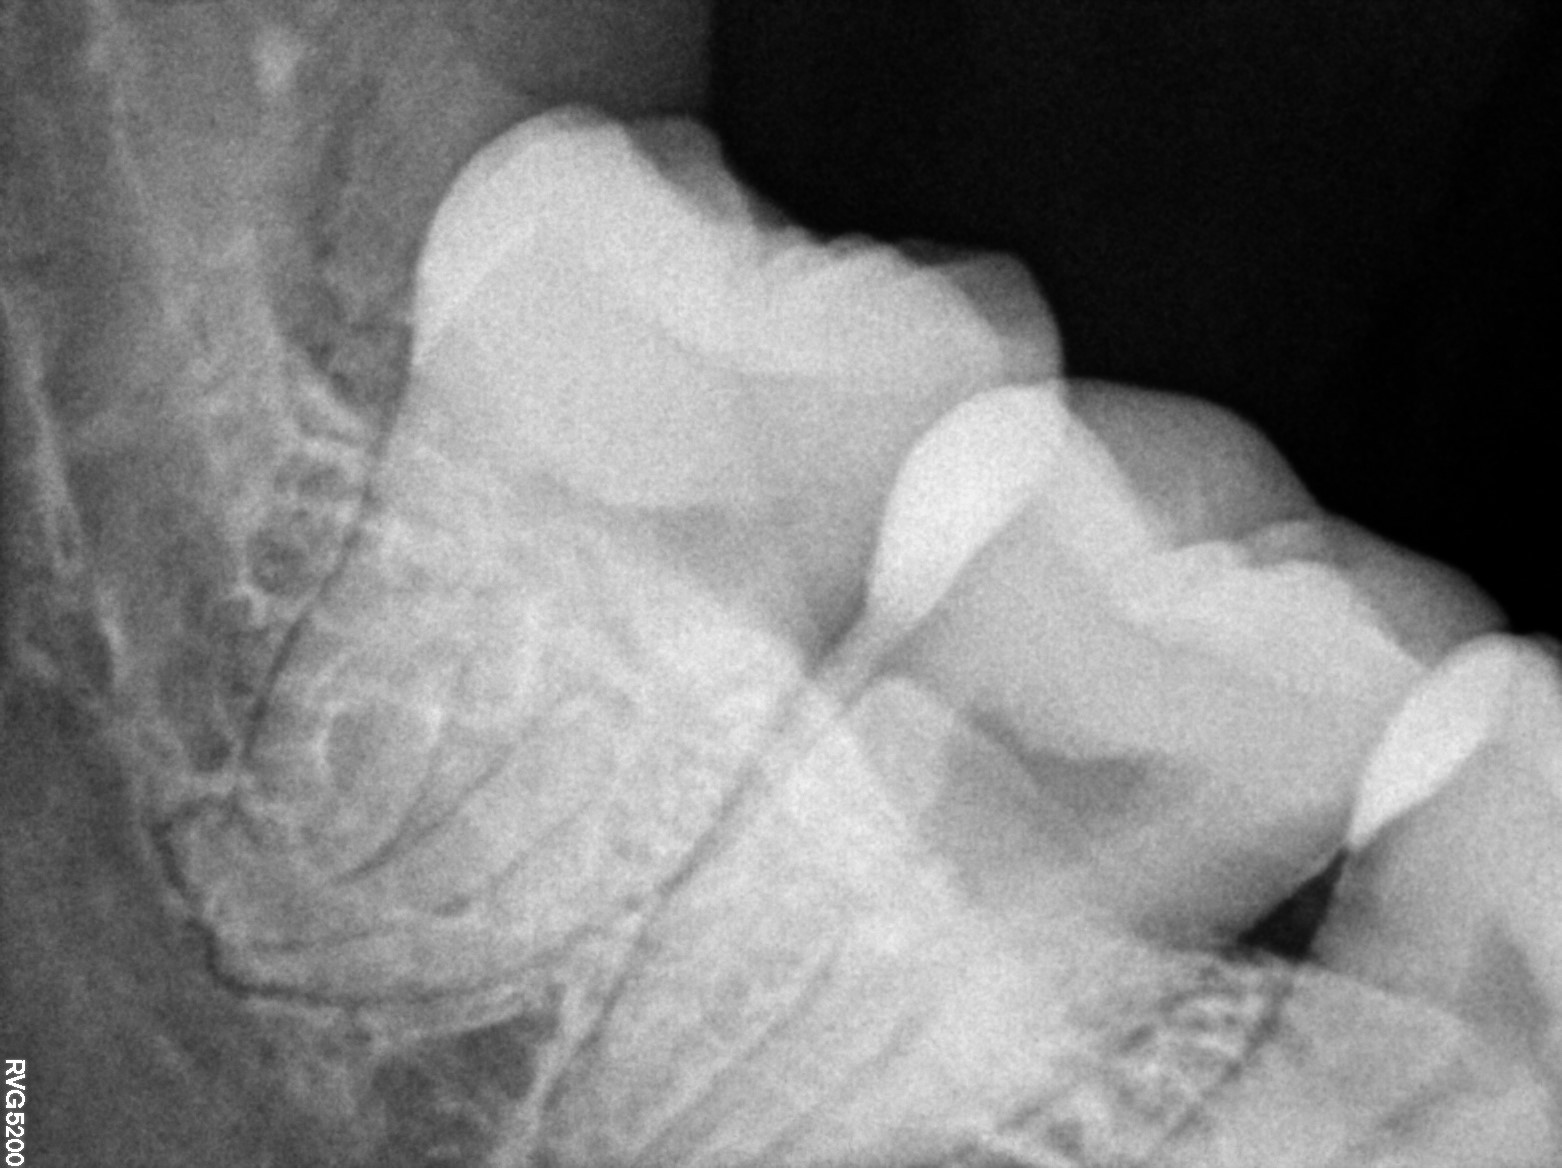

Dental Radiographs FHIR: DocumentReference · LOINC 24641-7

xray_1773646340_0.jpg

24641-7